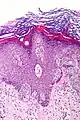

Leukaemia Lymphoma

- Lymphoma and myeloma, derived from cells of the immune system.

Cancer cells have distinguishing histological features visible under the microscope. The nucleus is often large and irregular, and the cytoplasm may also display abnormalities.[3]

Nucleus

The shape, size, protein composition, and texture of the nucleus are often altered in malignant cells. The nucleus may acquire grooves, folds or indentations, chromatin may aggregate or disperse, and the nucleolus can become enlarged. In normal cells, the nucleus is often round or solid in shape, but in cancer cells the outline is often irregular. Different combinations of abnormalities are characteristic of different cancer types, to the extent that nuclear appearance can be used as a marker in cancer diagnostics and staging.[4]